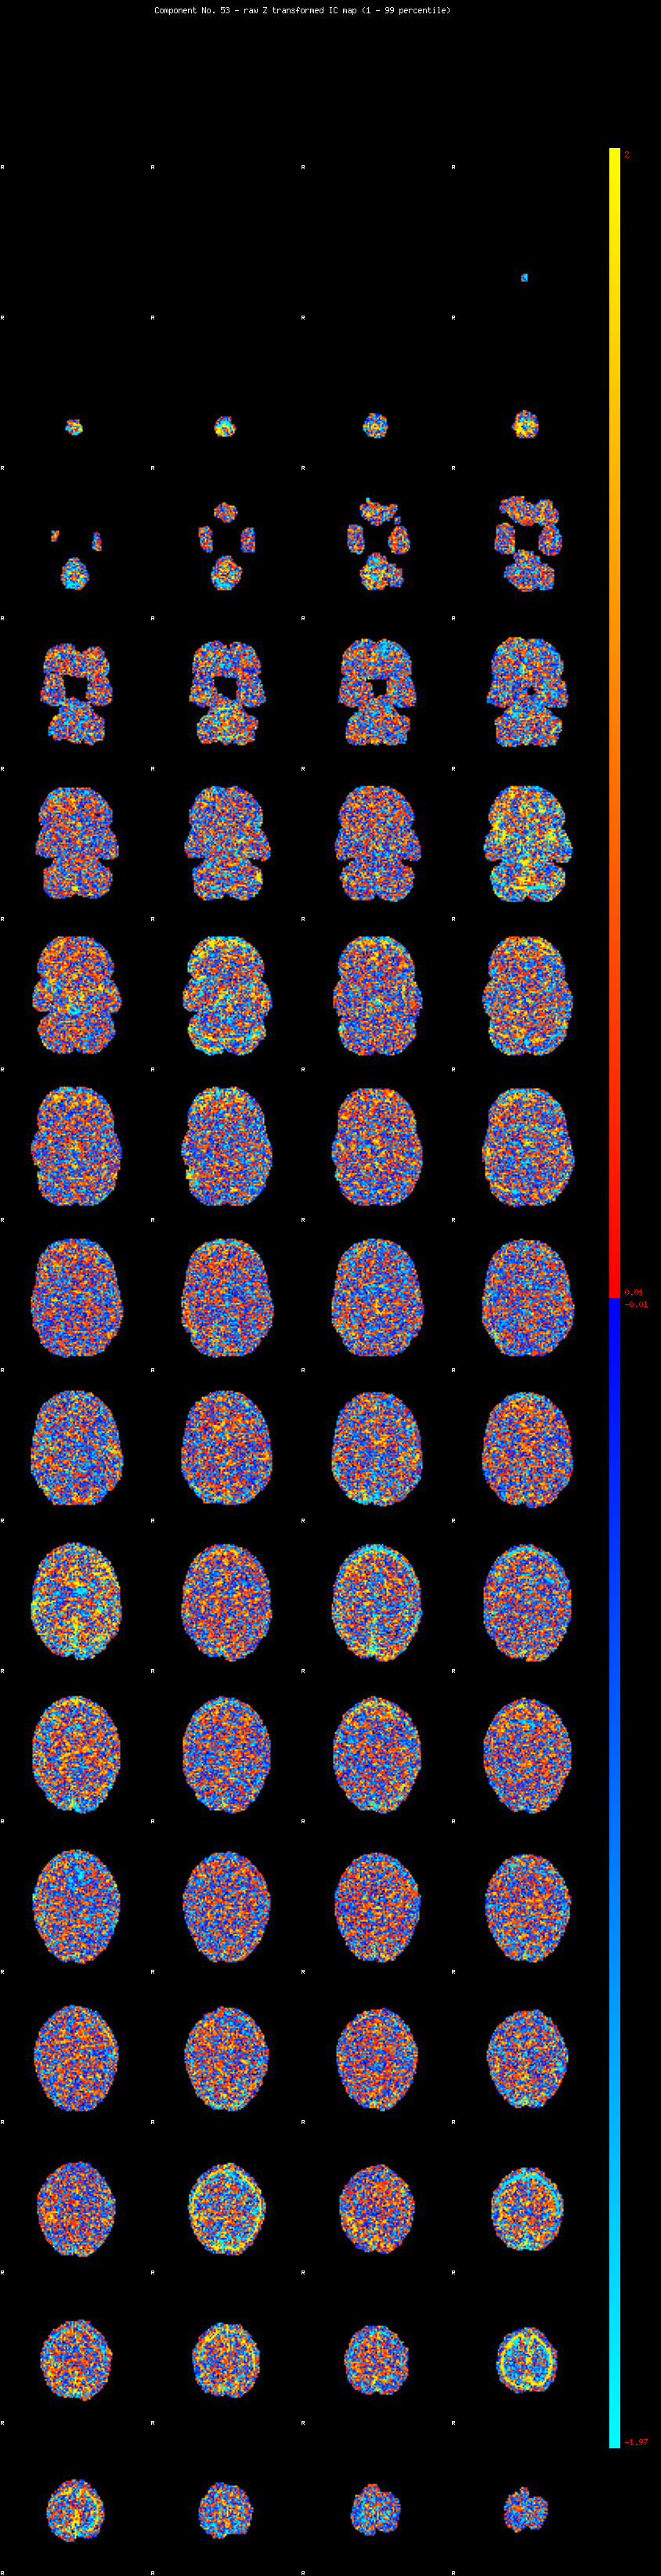

IC_53 Mixture Model fit

Means : 0.000000 2.430989 -2.231966

Vars : 1.000000 1.849518 1.262127

Prop. : 0.932262 0.033590 0.034148